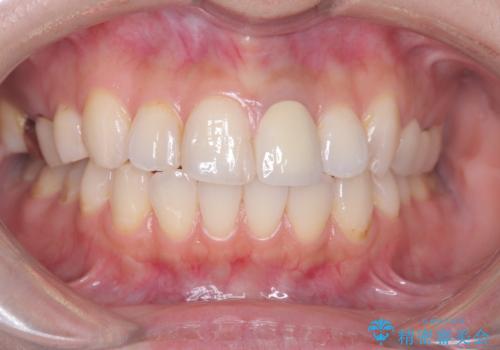

オールセラミッククラウンで治療を行い見た目の改善を行いました。

右上1もCRが入っており治療を勧めましたが、希望されず左上1のみ行いました。

色味は左上2に合わせたいとのご希望だったので、左上2に合わせています。